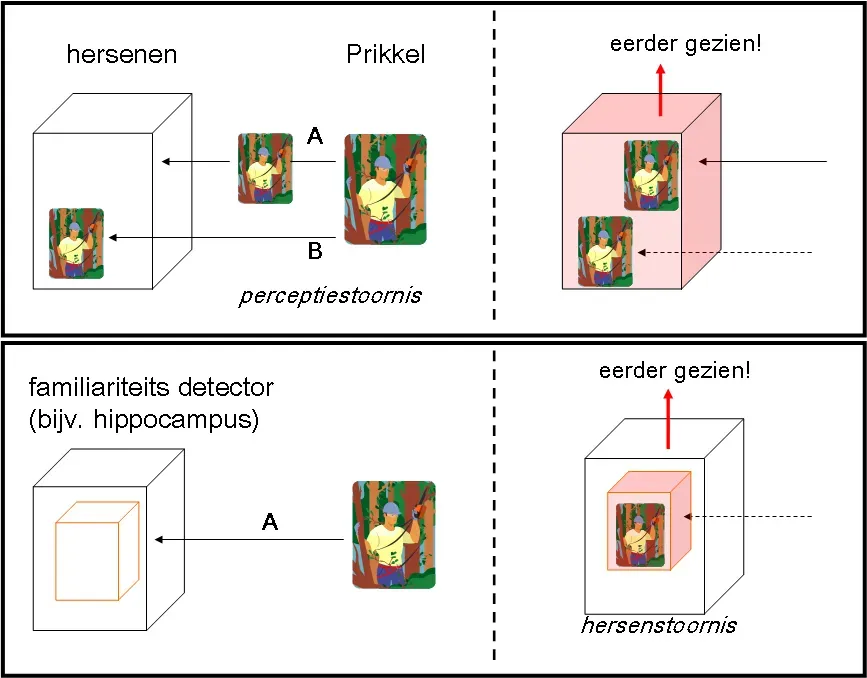

To understand deja vu, it helps to picture memory not as a single filing cabinet but as a network of specialized systems. One part of the brain is especially good at storing the “what, where, and when” of events, while another handles the raw gut-sense that something is familiar. The hippocampus and surrounding medial temporal lobe structures help encode detailed episodic memories, like a birthday party or a first day at work. Meanwhile, regions such as the parahippocampal cortex act more like a familiarity detector, sending a quick yes-or-no signal about whether something has been encountered before. Deja vu appears when this familiarity signal goes rogue.

Most of the time, those systems work together seamlessly, so that a feeling of recognition comes bundled with specific recollection. In a deja vu episode, however, brain imaging and theoretical models suggest that familiarity may flare up alone, without the hippocampus providing the missing details. The result is a strange hybrid state where the brain insists that the scene is known but cannot supply the supporting evidence. Some researchers compare it to an internal quality-control flag, where awareness notices the mismatch and briefly audits its own processes. That internal audit, uncomfortable as it feels, may be one reason why healthy people with intact reality testing experience deja vu as fleeting rather than delusional.